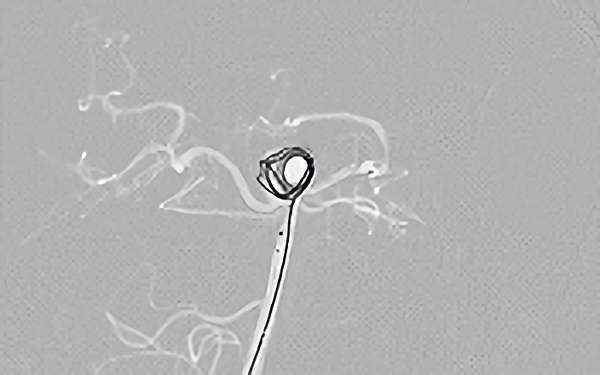

No.1628 手術前

No.1628 手術中

No.1628 手術後